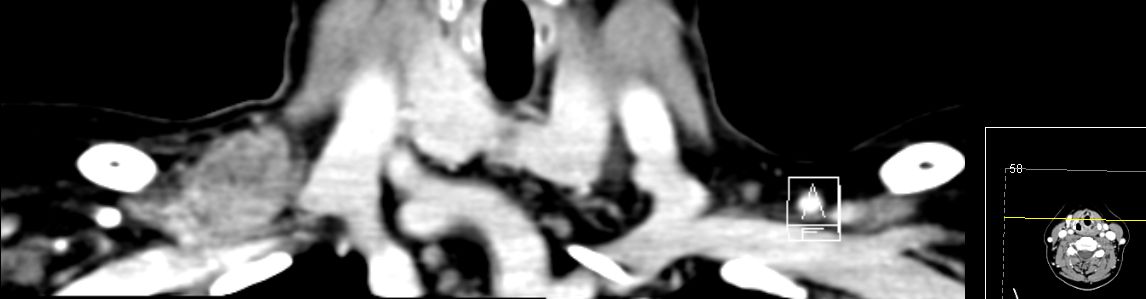

75-jährige Frau mit triple-negativem

Mammakarzinom. Chemotherapie abgelehnt. Im Planungs-CT

Lymphknotenvergrößerung mediastinal und parasernal.![]() | ||